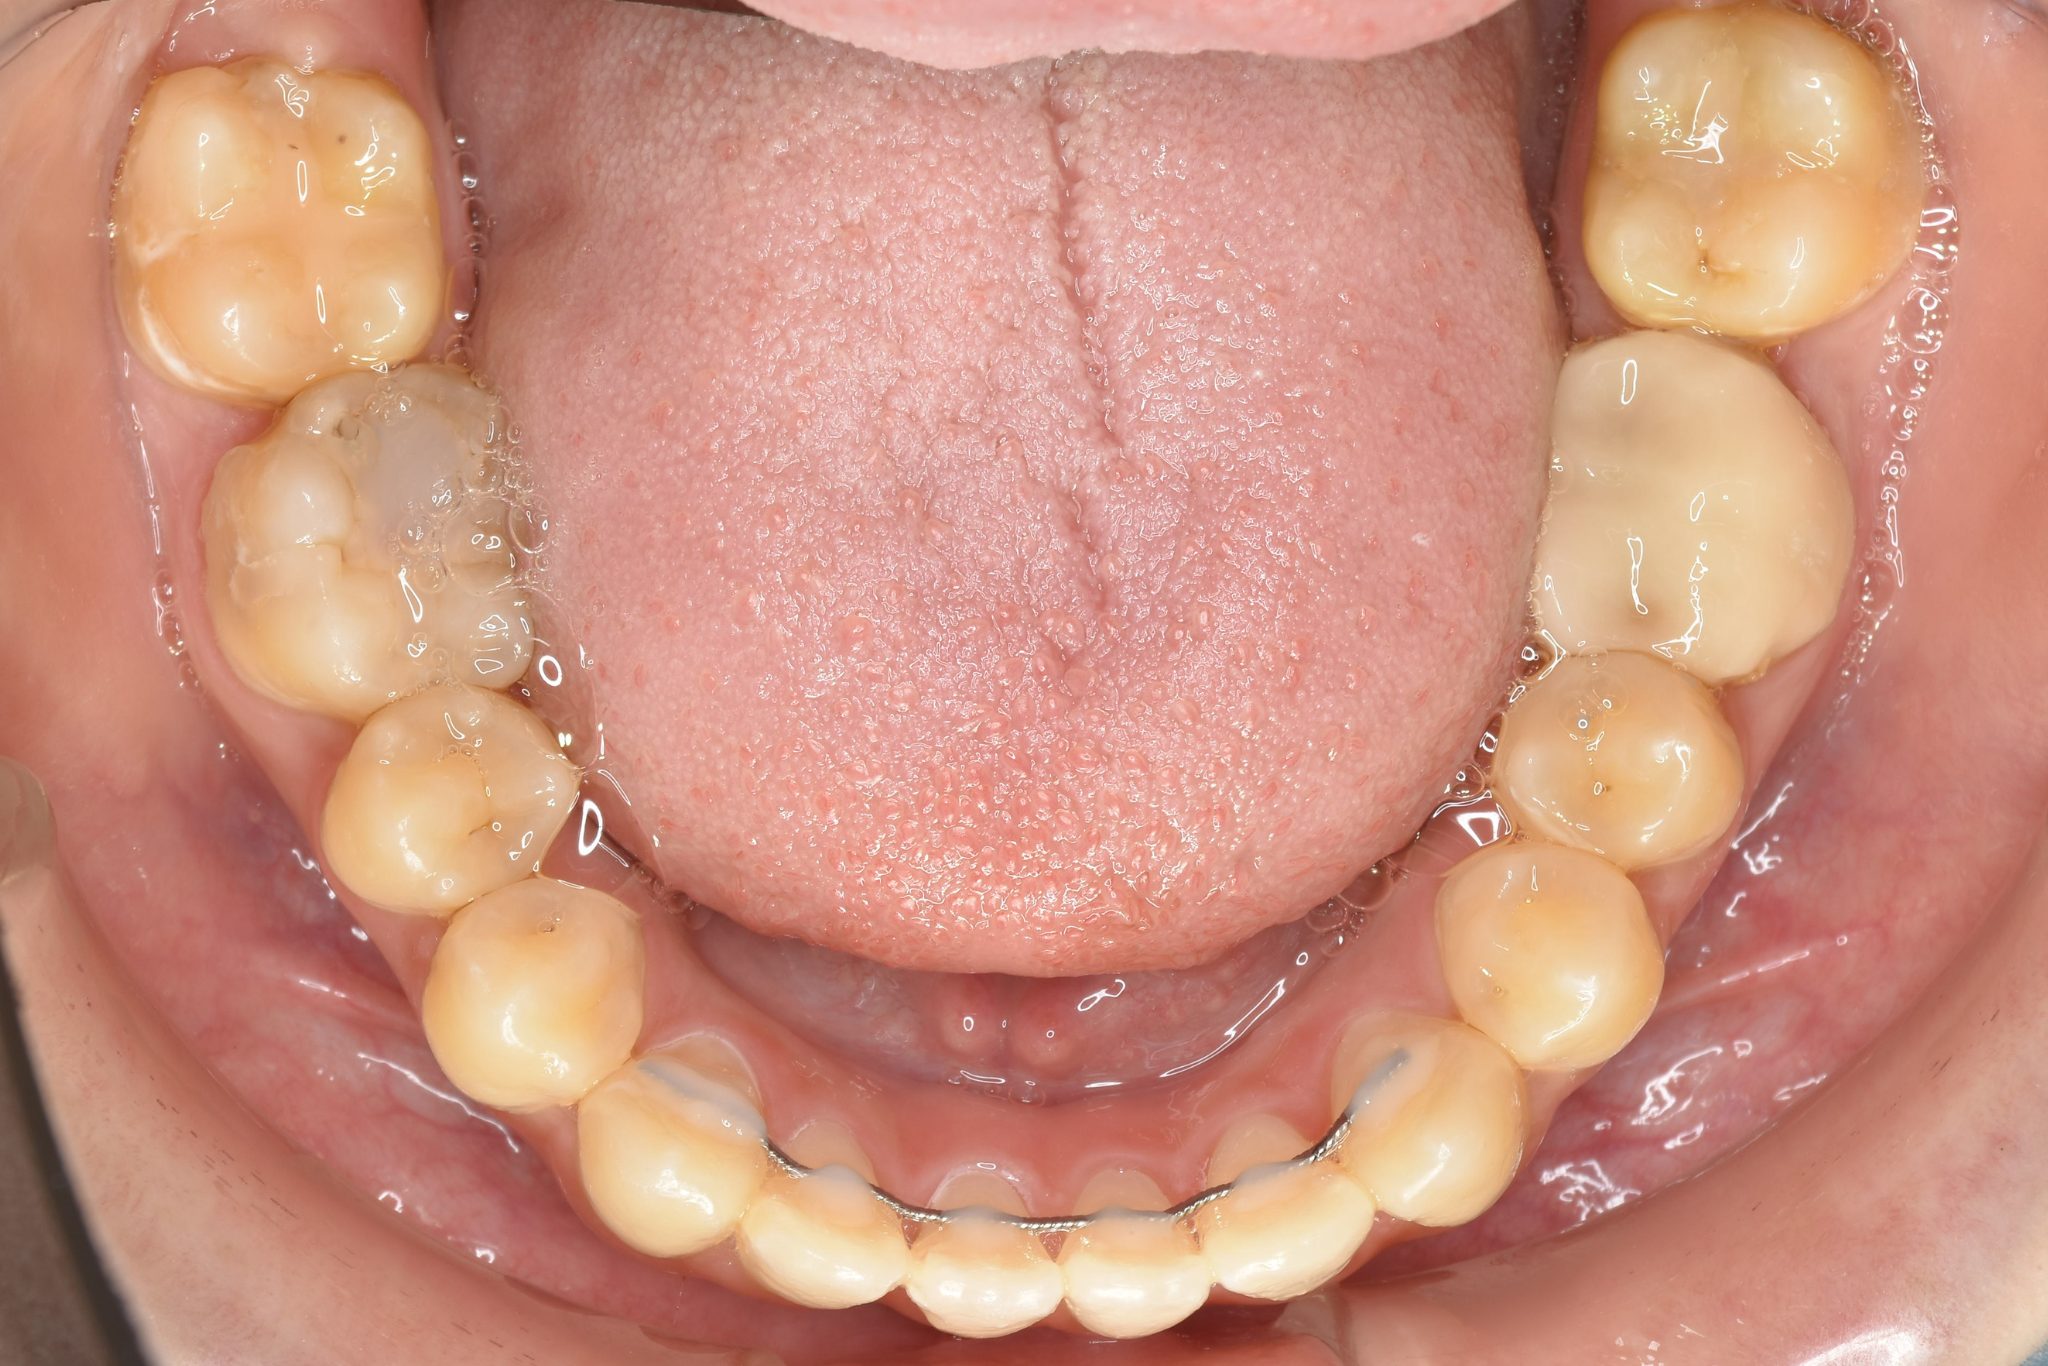

ビフォー

ワイヤー矯正治療|症例_032

主訴 歯並び|かみ合わせ

施術内容 MSEと下顎リンガルアーチを用いて上下顎骨を拡大した。

その後マルチブラケット装置を用いて非抜歯で歯牙を配列し良好な咬合を獲得した。

吸指癖と鼻閉症状は改善した。